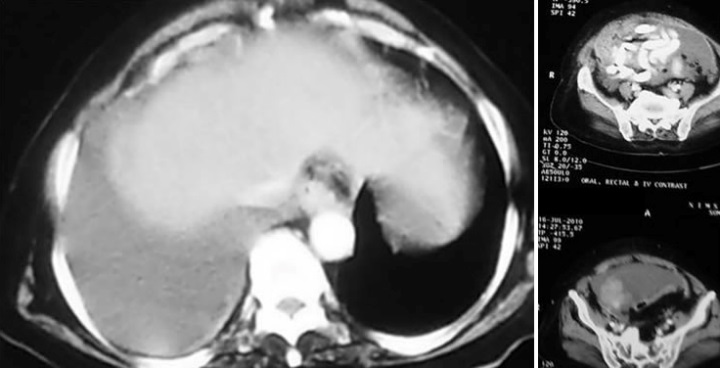

Stage 4: distant metastases, pleural effusion, pleural nodules or focal thickening suggest this stage. Accuracy for detecting peritoneal deposits is dependent on their location, size and presence of ascites. MRI and CT have similar sensitivity in detection of peritoneal deposits greater than 1cm. Peritoneal deposits appear has rounded, cake like, stellate or ill-defined masses. However deposits in mesentery/ implant on surface of bowel and calcified deposits are better seen in CT. Adjacent pelvic organ involvement may be difficult to diagnose accurately. In large ovarian tumour, it may be difficult to identify uterus which is partially or completely surrounded by tumour. Pelvic side wall invasion is suspected when tumour lies within 3mm of pelvic side wall or when iliac vessel are surrounded or displaced by tumour. Focal obliteration of fat plane or tumour encasement of bladder or recto sigmoid is highly suspicious of involvement of the structures. Staging accuracy is 80-90% (Figures 9 & 10).

Figure 9: Carcinoma of ovary stage 4 disease pleural effusion.

Figure 10: Omental caking with carcinoma of the ovary.